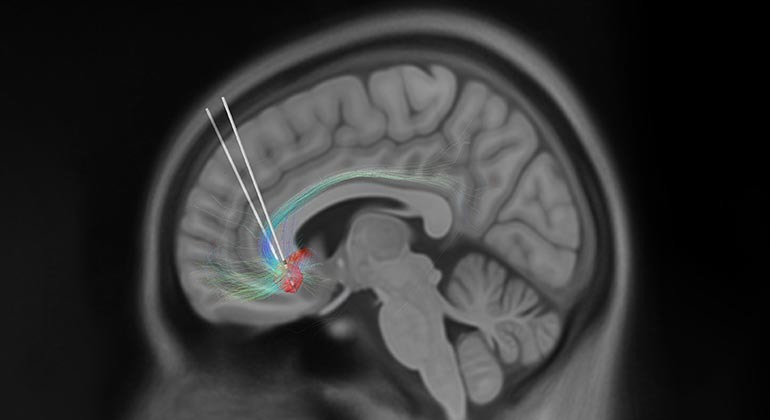

Важность Размещения Электродов на Операции по ГСМ

Точность установки электродов имеет первостепенное значение для успеха операции по Глубокой Стимуляции Мозга (ГСМ). Правильное расположение электродов в целевых областях мозга обеспечивает оптимальную подачу электрических импульсов и, таким образом, максимальное облегчение симптомов. Неправильное расположение может привести к неоптимальным результатам или, в некоторых случаях, к неблагоприятным последствиям, которые могут негативно повлиять на качество жизни пациента. Передовые методы нейровизуализации и интраоперационные электрофизиологические исследования являются важнейшими инструментами, которые помогают нейрохирургам добиться точного размещения электродов, что подчеркивает сложность и точность, требуемые при проведении процедур ГСМ. В связи с этими реалиями в нашем Центре Нейромодуляции мы предпочитаем проводить операции, когда пациент находится в сознании. Это позволяет нам точно определить оптимальную зону размещения электродов для каждого пациента, обеспечивая наилучший и наиболее продолжительный положительный эффект.